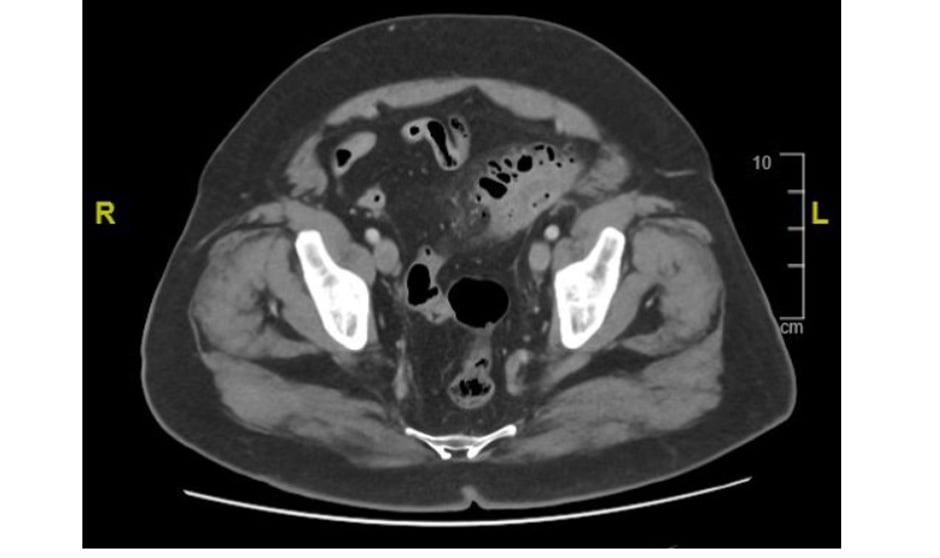

20. Pregunta asociada a la imagen 20.

Imagen 20.

Hombre de 73 años con antecedentes de hipertensión arterial y diabetes mellitus tipo 2 que acude a urgencias por presentar desde hace una semana hiperglucemia mayor de 500 mg/dL. Refiere que comenzó con dolor en vacío derecho y vómitos autolimitados. Desde entonces, disminución de la ingesta, poliuria y sensación distérmica sin fiebre termometrada. Se realiza ecografía y TC abdominopélvica sin contraste intravenoso que se muestra en la imagen. ¿Cuál de los siguientes es el diagnóstico más probable?:

1. Pielonefritis enfisematosa obstructiva.